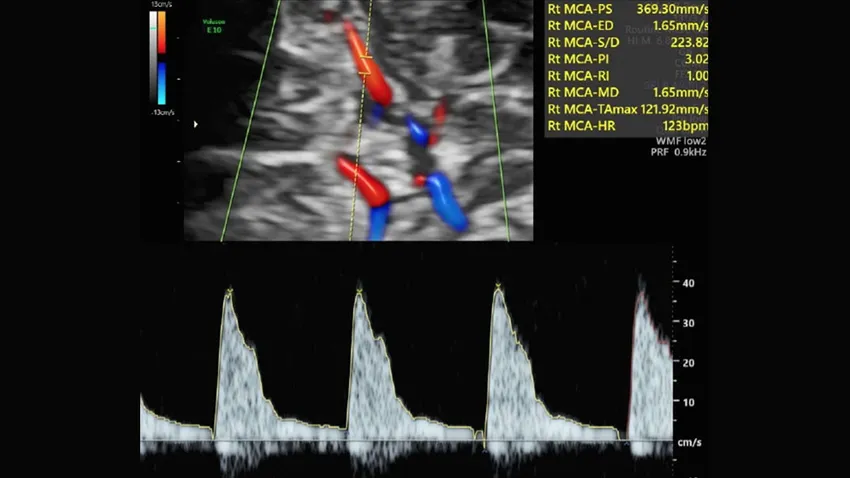

(Fundación ˝la Caixa˝).- Determinar el flujo de los vasos del cerebro del feto y de la placenta mediante Doppler en la ecografía de rutina del tercer trimestre permite detectar a bebés en riesgo de presentar complicaciones posparto que requieran ingreso en la UCI. Inducir el parto al término de la gestación en esos casos de riesgo podría reducir a la mitad la tasa de ingreso en la UCI neonatal. Así lo demuestra un estudio internacional multicéntrico denominado RATIO37 y publicado en la revista The Lancet.

Una prueba con ecografía Doppler que mide la circulación de la sangre por el cordón umbilical y el cerebro, denominada ratio cerebro-placentario (o RCP), puede detectar la insuficiencia placentaria. Hasta ahora, esta prueba solo se realizaba en embarazos con problemas, en casos muy indicados. Desde hace más de 10 años ha existido un debate en el mundo científico sobre si había que medir el RCP en todas las embarazadas o era un gasto de recursos innecesario. Si la prueba Doppler se llevara a cabo en todos los embarazos, tal vez serviría para mejorar la detección de bebés con riesgo de complicaciones por insuficiencia placentaria. Pero también existiría el riesgo de que la prueba no mejorase nada y, en cambio, solo generase más gasto y angustia en las madres.

En el estudio RATIO37 han participado durante 6 años más de 11.500 mujeres con embarazos de bajo riesgo. En la ecografía de las 36 semanas se midió el RCP en todas las mujeres, pero las participantes fueron divididas al azar en dos grupos. En unas, la prueba se utilizaba para cambiar el manejo de la gestación y, en caso de salir alterada, se proponía a la mujer una inducción precoz del parto al llegar al término. En las otras, el resultado de la prueba no se comunicaba y se manejaba el embarazo según los protocolos vigentes. El estudio comparó los números de casos de muerte del bebé y de complicaciones neonatales graves (que incluían, entre otros, problemas neurológicos, intestinales, cardíacos, renales o respiratorios, con una estancia en la UCI de 10 días o más) que se producían en cada grupo.